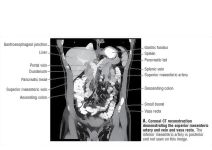

Angiograms of the Superior and Inferior Mesenteric Vessels